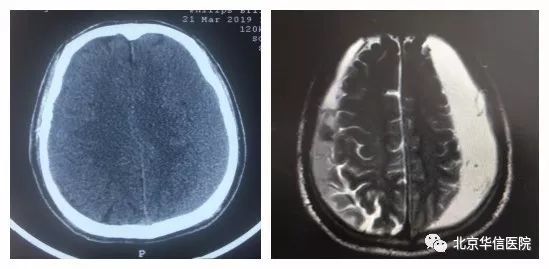

一位69岁老年男性患者,自诉2个月前骑自行车摔倒,近一个多月出现步态不稳,行走时右脚拖沓,并逐渐出现全身乏力及僵硬感。3月21日,患者来北京华信医院(清华大学第一附属医院)神经内科以帕金森综合征收住院治疗,通过头颅CT检查提示:双侧慢性硬膜下血肿,出血量很大,以左侧居多。于是转入神经外科治疗,完善头颅MR检查,明确诊断。期间患者症状逐渐加重,意识朦胧,急诊在全麻下行双侧慢性硬膜下血肿钻孔引流术,术中左侧引流出陈旧性血液量约80ml,右侧引流出陈旧性血液体量约40ml,术后患者右侧肢体活动明显好转,活动自如,意识很快清醒。持续引流2天后,复查头颅CT,血肿清除,术后第3天拔出穿刺针,患者目前已治愈出院。

术前头颅CT(左)和MRI(右)